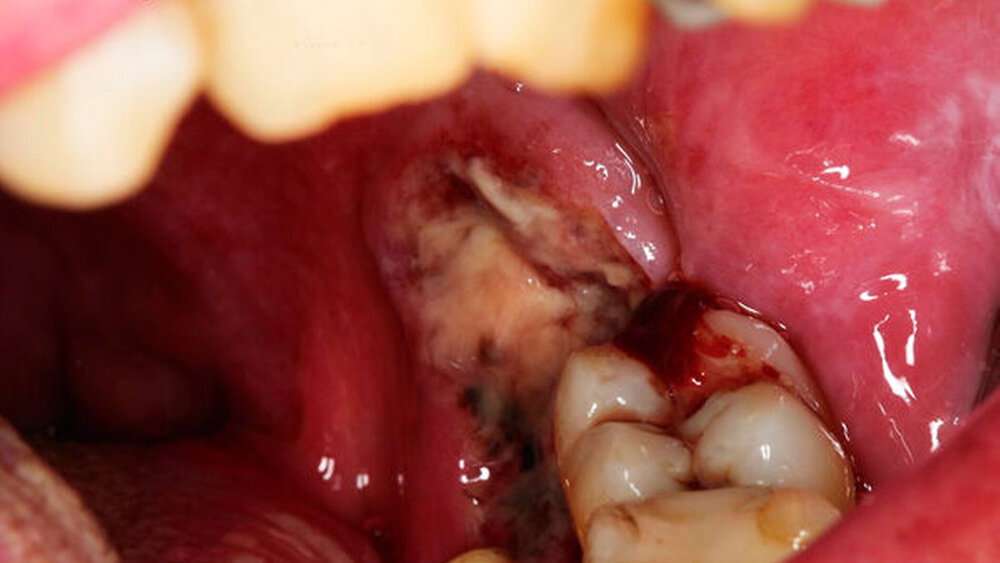

Ein 52-jähriger Patient stellte sich mit einer fortgeschrittenen Parodontitis und einer schweren Gingivitis in der Klinik und Poliklinik für Mund-, Kiefer- und Gesichtschirurgie der Universitätsmedizin Mainz vor. Die Überweisung durch den Hauszahnarzt war aufgrund einer sich in regio 38 befindlichen ulzerierten Raumforderung mit Verdacht auf das Vorliegen eines Plattenepithelkarzinoms erfolgt.

In der klinischen Untersuchung zeigte sich eine starke generalisierte Parodontitis mit ubiquitär zweit- bis drittgradig gelockerten Zähnen. Der Patient litt weiterhin unter einer starken Gingivitis mit geröteter und geschwollener Schleimhaut. Er berichtete über zahlreiche Versuche der Parodontaltherapie, die jedoch lediglich zu Blutungen, Schmerzen und einem weiteren Rückgang der Schleimhaut geführt hätten. In regio 38 zeigte sich ein etwa 3 cm x 3 cm großer, ulzerierender Befund, der sich über den aufsteigenden Ast des Unterkiefers bis nach lingual erstreckte und zu Teilen den noch vorhandenen Zahn 37 umschloss (Abbildung 1). Der Patient gab in diesem Bereich starke Schmerzen an, die Mundöffnung war deutlich eingeschränkt. Auch zeigte sich ein Foetor ex ore. Neben der akuten klinischen Symptomatik berichtete der Patient über keine bekannten Vorerkrankungen außer einem Nikotinabusus von 35 Packungsjahren.